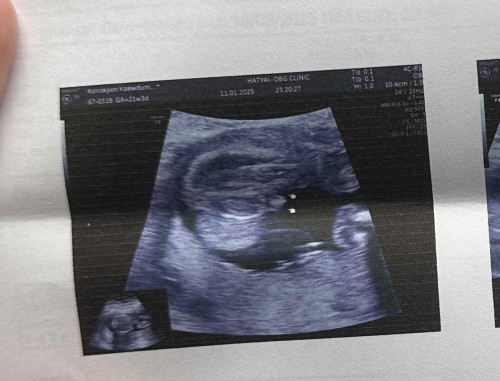

ไปอัลตราซาวด์มาวันนี้ 21 สัปดาห์ 4วัน หมอคอนเฟิร์มว่าน้องเป็นผู้ชาย 100% แต่ใจคุณแม่อยากได้ผู้หญิงมากมีโอกาสจะย้ายทีมไหมคะ🥹🤣